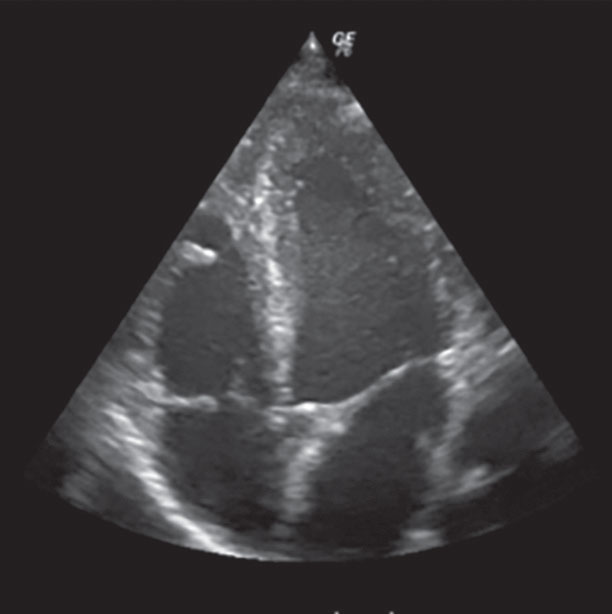

А вот для многих других ситуаций это просто замечательный метод: быстрый, недорогой, доступный. Можно посмотреть на щитовидную железу или на почки. Можно увидеть состояние органов брюшной полости. Можно наблюдать за строением и работой сердца — это называется эхокардиографией. Можно узнавать о том, с какой скоростью кровь движется по сосудам. Можно понаблюдать за развитием ещё не родившегося ребёнка — насколько нам сейчас известно, для него ультразвук (в отличие от многих других видов исследований) совершенно безвреден.

Сердце на УЗИ. Видны 4 камеры, перегородки и клапаны